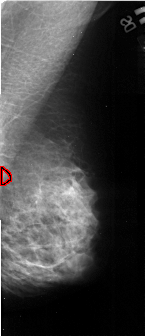

A_1041_1.RIGHT_MLO

RIGHT_MLO LINES 5026 PIXELS_PER_LINE 2161 BITS_PER_PIXEL 16 RESOLUTION 42 OVERLAY

FILE: A_1041_1.RIGHT_MLO.OVERLAY

TOTAL_ABNORMALITIES 1

ABNORMALITY 1

LESION_TYPE CALCIFICATION TYPE PLEOMORPHIC DISTRIBUTION CLUSTERED

ASSESSMENT 4

SUBTLETY 2

PATHOLOGY MALIGNANT

TOTAL_OUTLINES 1

BOUNDARY